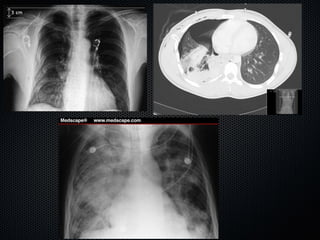

Realizar estudos de imagem prontamente para confirmar

e amostrar eventual foco infeccioso (se isto for seguro)

Surviving Sepsis Campaign. Crit Care Med 2013 41(2): 580-637